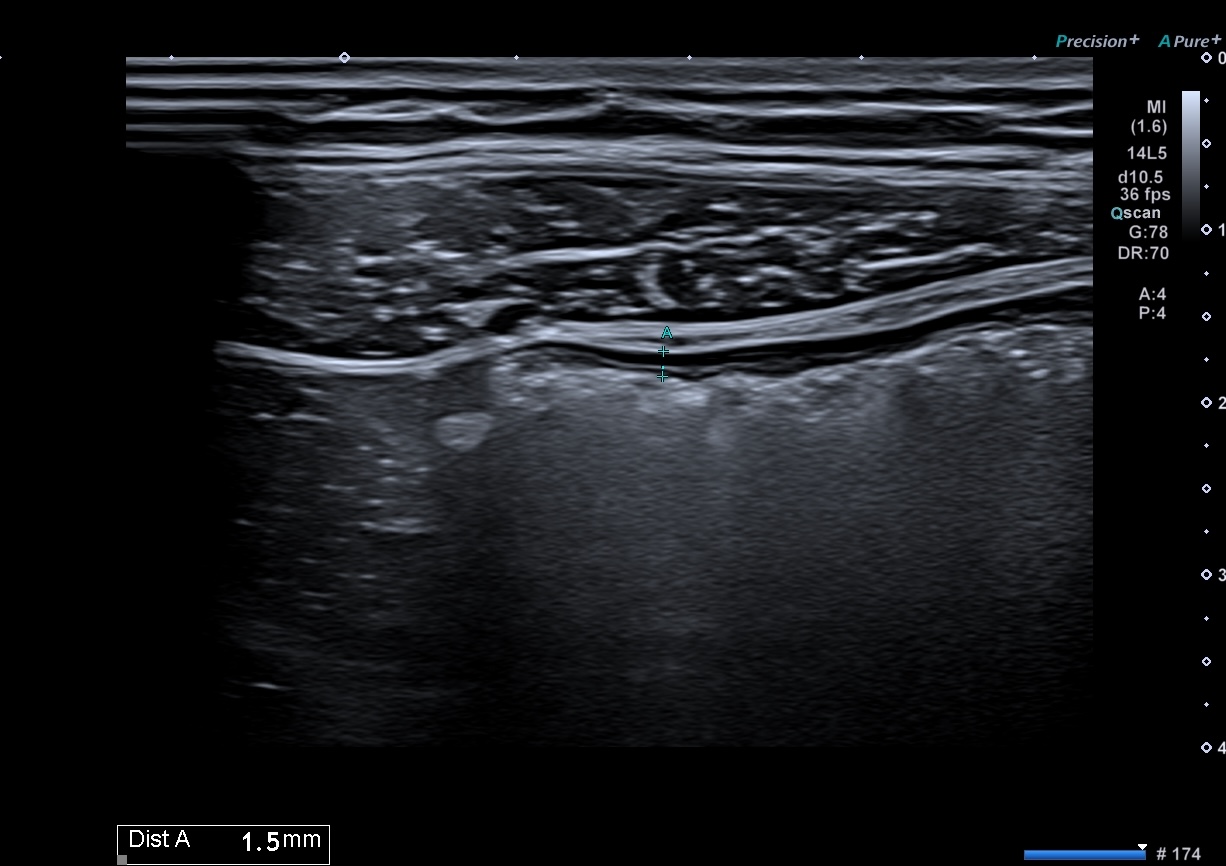

Echographie 22/12/2022

En échographie la colite aigüe grave se traduit par

1. Epaississement important :

une inflammation au delà de 8 mm, voir 10 ou exceptionnellement 12 mm est un signe de gravité.

2. la disparition de la structure en couches

L’inflammation qui dans la RCH est au départ superficielle (couches 2 et 3) gagne la totalité de la paroi (la sous muqueuse devient hypoéchogène et toute la paroi devient noire hypoéchogène)

Epaississement considérable par endroit (10 ou 11 mm), disparition totale de la structure en couches, déformation de la surface avec ulcérations, déformation des contours, infiltration de la graisse, hyperactivité Doppler

Le Score de Milan (MUC) est à 17.4

Les images échographiques correspondent parfaitement aux images endoscopiques, et sont finalement beaucoup plus précises que les images scanographiques.